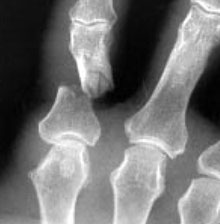

Metacarpal fracture of ring finger and surgical repair.

Reproduced with permission from Kozin SH, Thoder JJ, Lieberman G: Operative Treatment of Metacarpal and Phalangeal Shaft Fractures. J Am Acad Orthop Surg 2000;8:111-121.

Some hand fractures require surgery to stabilize and align the bones. These fractures usually break through the skin or result from a crushing accident. An orthopaedic surgeon can implant wires, screws, or plates in the broken bone to hold the pieces of the fractured bone in place.